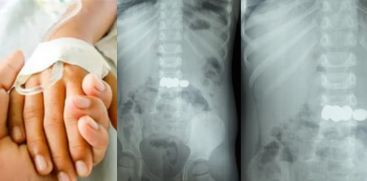

മേപ്പാടി: കളിക്കുന്നതിനിടെ 2 വയസുകാരൻ അബദ്ധത്തിൽ വിഴുങ്ങിയത് 5 ബാറ്ററികൾ.  ബത്തേരി മൂലങ്കാവ് സ്വദേശികളായ ദമ്പതികളുടെ മകനാണ് കളിപ്പാട്ടത്തിലെ ബാറ്ററികൾ വിഴുങ്ങിയത്.കളിപ്പാട്ടത്തിലെ കോയിൻ ടൈപ്പ് ബാറ്ററികൾ ആണ് വിഴുങ്ങിയത്. ഡോക്ടർമാരുടെ കൃത്യസമയത്തുള്ള ഇടപെടൽ മൂലം വലിയൊരു അപകടം ഒഴിവാക്കാനായി.കുട്ടി ബാറ്ററികൾ വായിലിടുന്നത് ശ്രദ്ധയിൽപ്പെട്ട വീട്ടുകാർ ഒട്ടും വൈകാതെ തന്നെ കുട്ടിയെ മെഡിക്കൽ കോളേജിലെത്തിച്ചു.

ഗാസ്‌ട്രോ എന്ററോളജി വിഭാഗം സ്പെഷ്യലിസ്റ്റ് ഡോ. സൂര്യനാരായണന്റെ നേതൃത്വത്തിലാണ് ബാറ്ററികൾ പുറത്തെടുക്കാനുള്ള നടപടികൾ ആരംഭിച്ചത്. എൻഡോസ്കോപ്പിയിലൂടെ അഞ്ച് ബാറ്ററികളും സുരക്ഷിതമായി പുറത്തെടുത്തു. ഡോ. അഖിൽ, ഡോ. അഞ്ജന എന്നിവരും ഈ ദൗത്യത്തിൽ പങ്കാളികളായി.ബാറ്ററികൾ വിഴുങ്ങുന്നത് ജീവന് തന്നെ ഭീഷണിയാണെന്ന് ഡോക്ടർമാർ മുന്നറിയിപ്പ് നൽകുന്നു: വയറ്റിലെ അസിഡിക് പ്രവർത്തനം മൂലം ബാറ്ററികൾ പൊട്ടിപ്പോകാൻ സാധ്യതയുണ്ട്. ബാറ്ററി പൊട്ടിയാൽ പുറന്തള്ളപ്പെടുന്ന രാസവസ്തുക്കൾ കുടൽ, കരൾ തുടങ്ങിയ പ്രധാന അവയവങ്ങൾക്ക് ഗുരുതരമായ നാശമുണ്ടാക്കും. കൃത്യസമയത്ത് എൻഡോസ്കോപ്പിയിലൂടെ ഇവ പുറത്തെടുക്കാൻ സാധിച്ചില്ലെങ്കിൽ സങ്കീർണ്ണമായ ശസ്ത്രക്രിയകളിലേക്ക് നീങ്ങേണ്ടി വരുമായിരുന്നു.